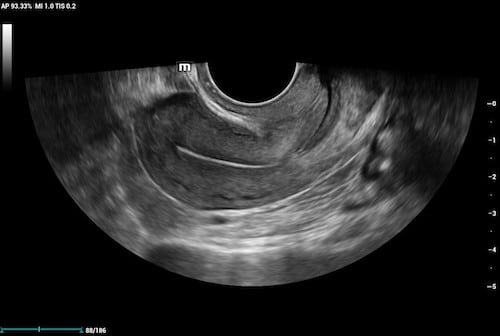

Endocavity Transducers

An endocavity transducer is a specialty transducer used to image structures from inside the body. This allows for better visualization of structures that are not easy to view with a surface transducer. The shape of the imaging surface provides a very wide field of view. Endocavity transducers are most frequently used for OB/GYN and urology applications.

2D image of uterus with an endocavity transducer